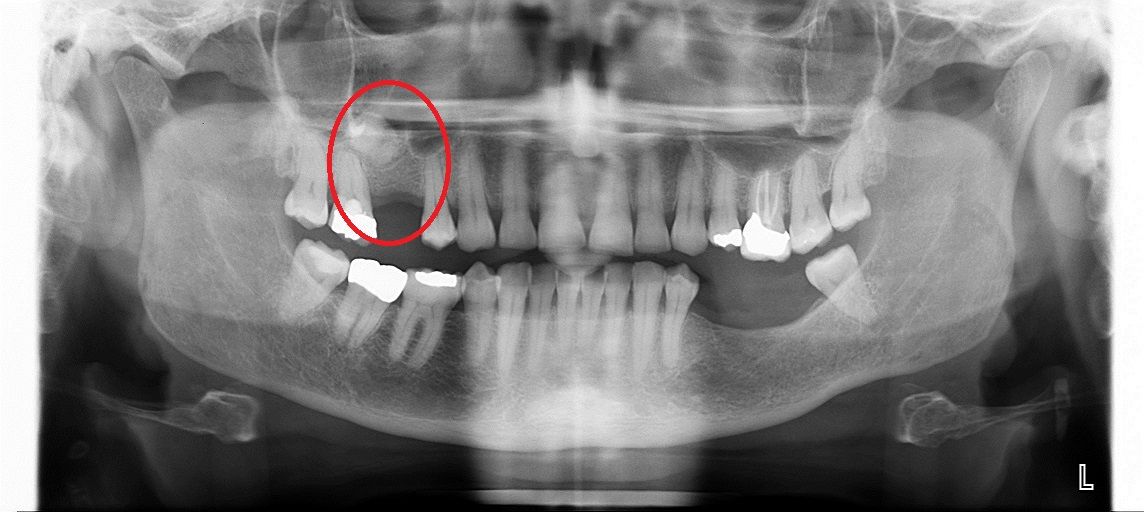

Синус лифтинг

После удаления зуба из-за отсутствия необходимой нагрузки на челюсть, кость в пустующем месте атрофируется. В этом случае перед имплантацией необходимо восполнить объем костной ткани.

Разновидность костной пластики направленной на увеличение объема костной ткани верхней челюсти в районе гайморовых пазух.

Открытый синус лифтинг

Открытый синус-лифтинг применяется, когда для установки имплантата не хватает более 3 мм костной ткани. При проведении этой операции имплантация в ряде случаев возможна только после полного восстановления кости челюсти.

• до синус-лифтинга

• после синус-лифтинга